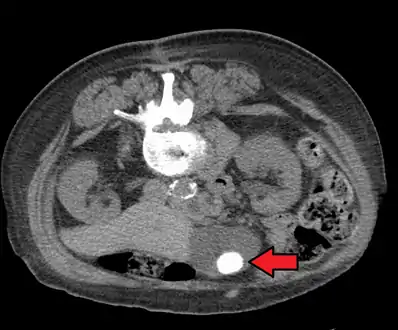

Gallstones as seen on plain X-ray

Large gallstone as seen on CT- A normal gallbladder on ultrasound with bowel peristalsis creating the false appearance of stones